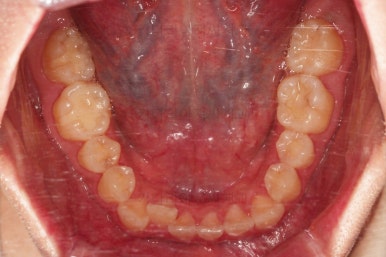

초기 6개월 이내에 어느 정도 치열이 가지런해 졌네요.

중간평가 들어갑니다.

앞니가 많이 뻗쳤나요?

그렇지 않죠.

대신 처음에는 삐뚤어서 가려져 있던 부정교합이 드러나면서 최소한 윗니는 교합을 위해 후방이동이 필요한 상황이긴 했습니다.